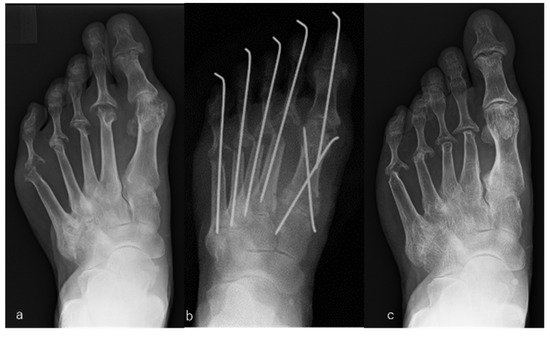

Figure 1.

Rheumatoid arthritis (RA) in a 78-year-old woman. Metatarsophalangeal joint-preserving surgery was performed involving the modified Mann method for the big toe and offset osteotomy for lesser toes. RA had been present for 6 years. The patient received bucillamine (200 mg/day) and sulfasalazine (1000 mg/day). Macrographic and radiographic views of her right foot before surgery (a,b), immediately after surgery (c), and 7 years after surgery, which was the latest follow-up (d). The score on the Japanese Society for Surgery of the Foot RA foot and ankle scale improved from 40 points before surgery to 92 points at the 7-year follow-up. The mean hallux valgus angle improved from 45° before surgery to 14° immediately after surgery and was 19° at the 7-year follow-up. The patient was satisfied with the clinical results at the 7-year follow-up, although the correction of the hallux valgus angle had decreased slightly compared with that immediately after surgery.